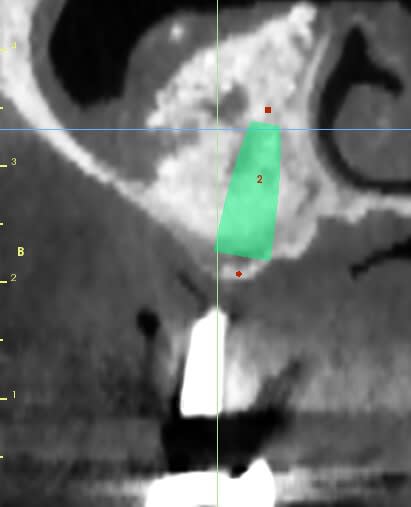

patiente ayant été implantée il y a 12 jours et toujours mal

le sinus lift a été pratiqué il y a 8 mois

les implants ont été posés sans problème, et le BM était bien dense

ce qui m'ennuie ce sont les douleurs 12 jours après l'implantation

Aspect lacunaire du biomat au scanner = sucre mouillé infecté...car non vivant et non vascularisé

bon je m'en doutais un peu que ça venait des lacunes dans le bio oss